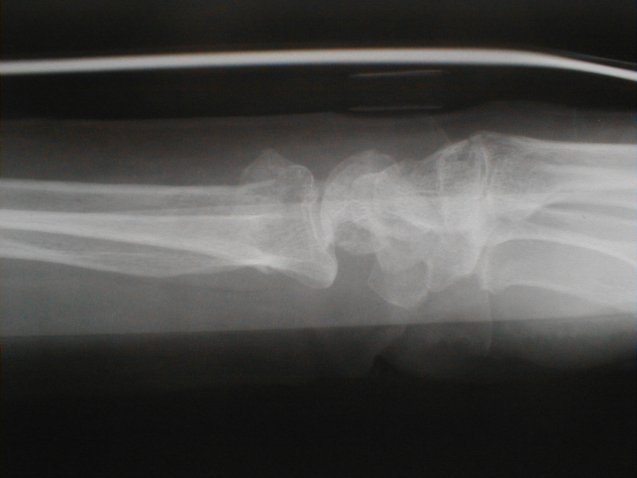

症例 9

左前腕骨骨折 コーレス骨折

72歳 女性

平成13年1月5日 七日目

包帯固定

橈骨が背側に転位しているのが、若干気になるが高齢者でもあり整復操作は愛護的におこなった

現在、日常動作にはまったく不自由なく生活している